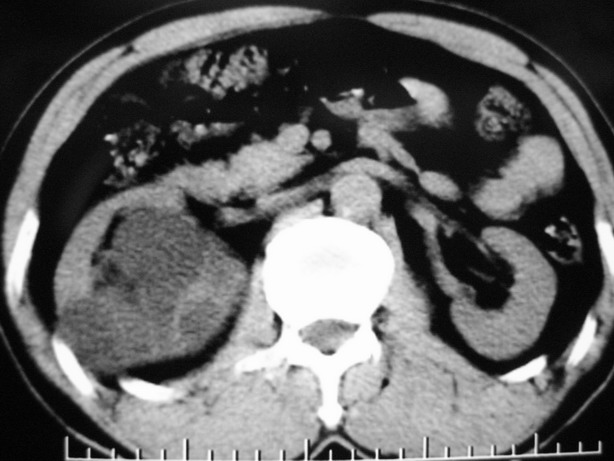

标题: CT10772:男性,48,右肾盂旁多囊性占位! [打印本页]

男性,48,体检发现,平时无症状。

增强:

肾盂旁多囊性占位,有实性成分,增强有轻度强化,收集期病变内无造影剂显影。诊断肾盂旁囊肿,有实性成分无法解释,查书后诊断为:多房性囊性肾瘤!!不知大家同意否?????????对本病知道不多,望大家不吝赐教!!

右肾多发囊性低密度影,囊内有增强的隔及实性组织,考虑囊性肾癌。